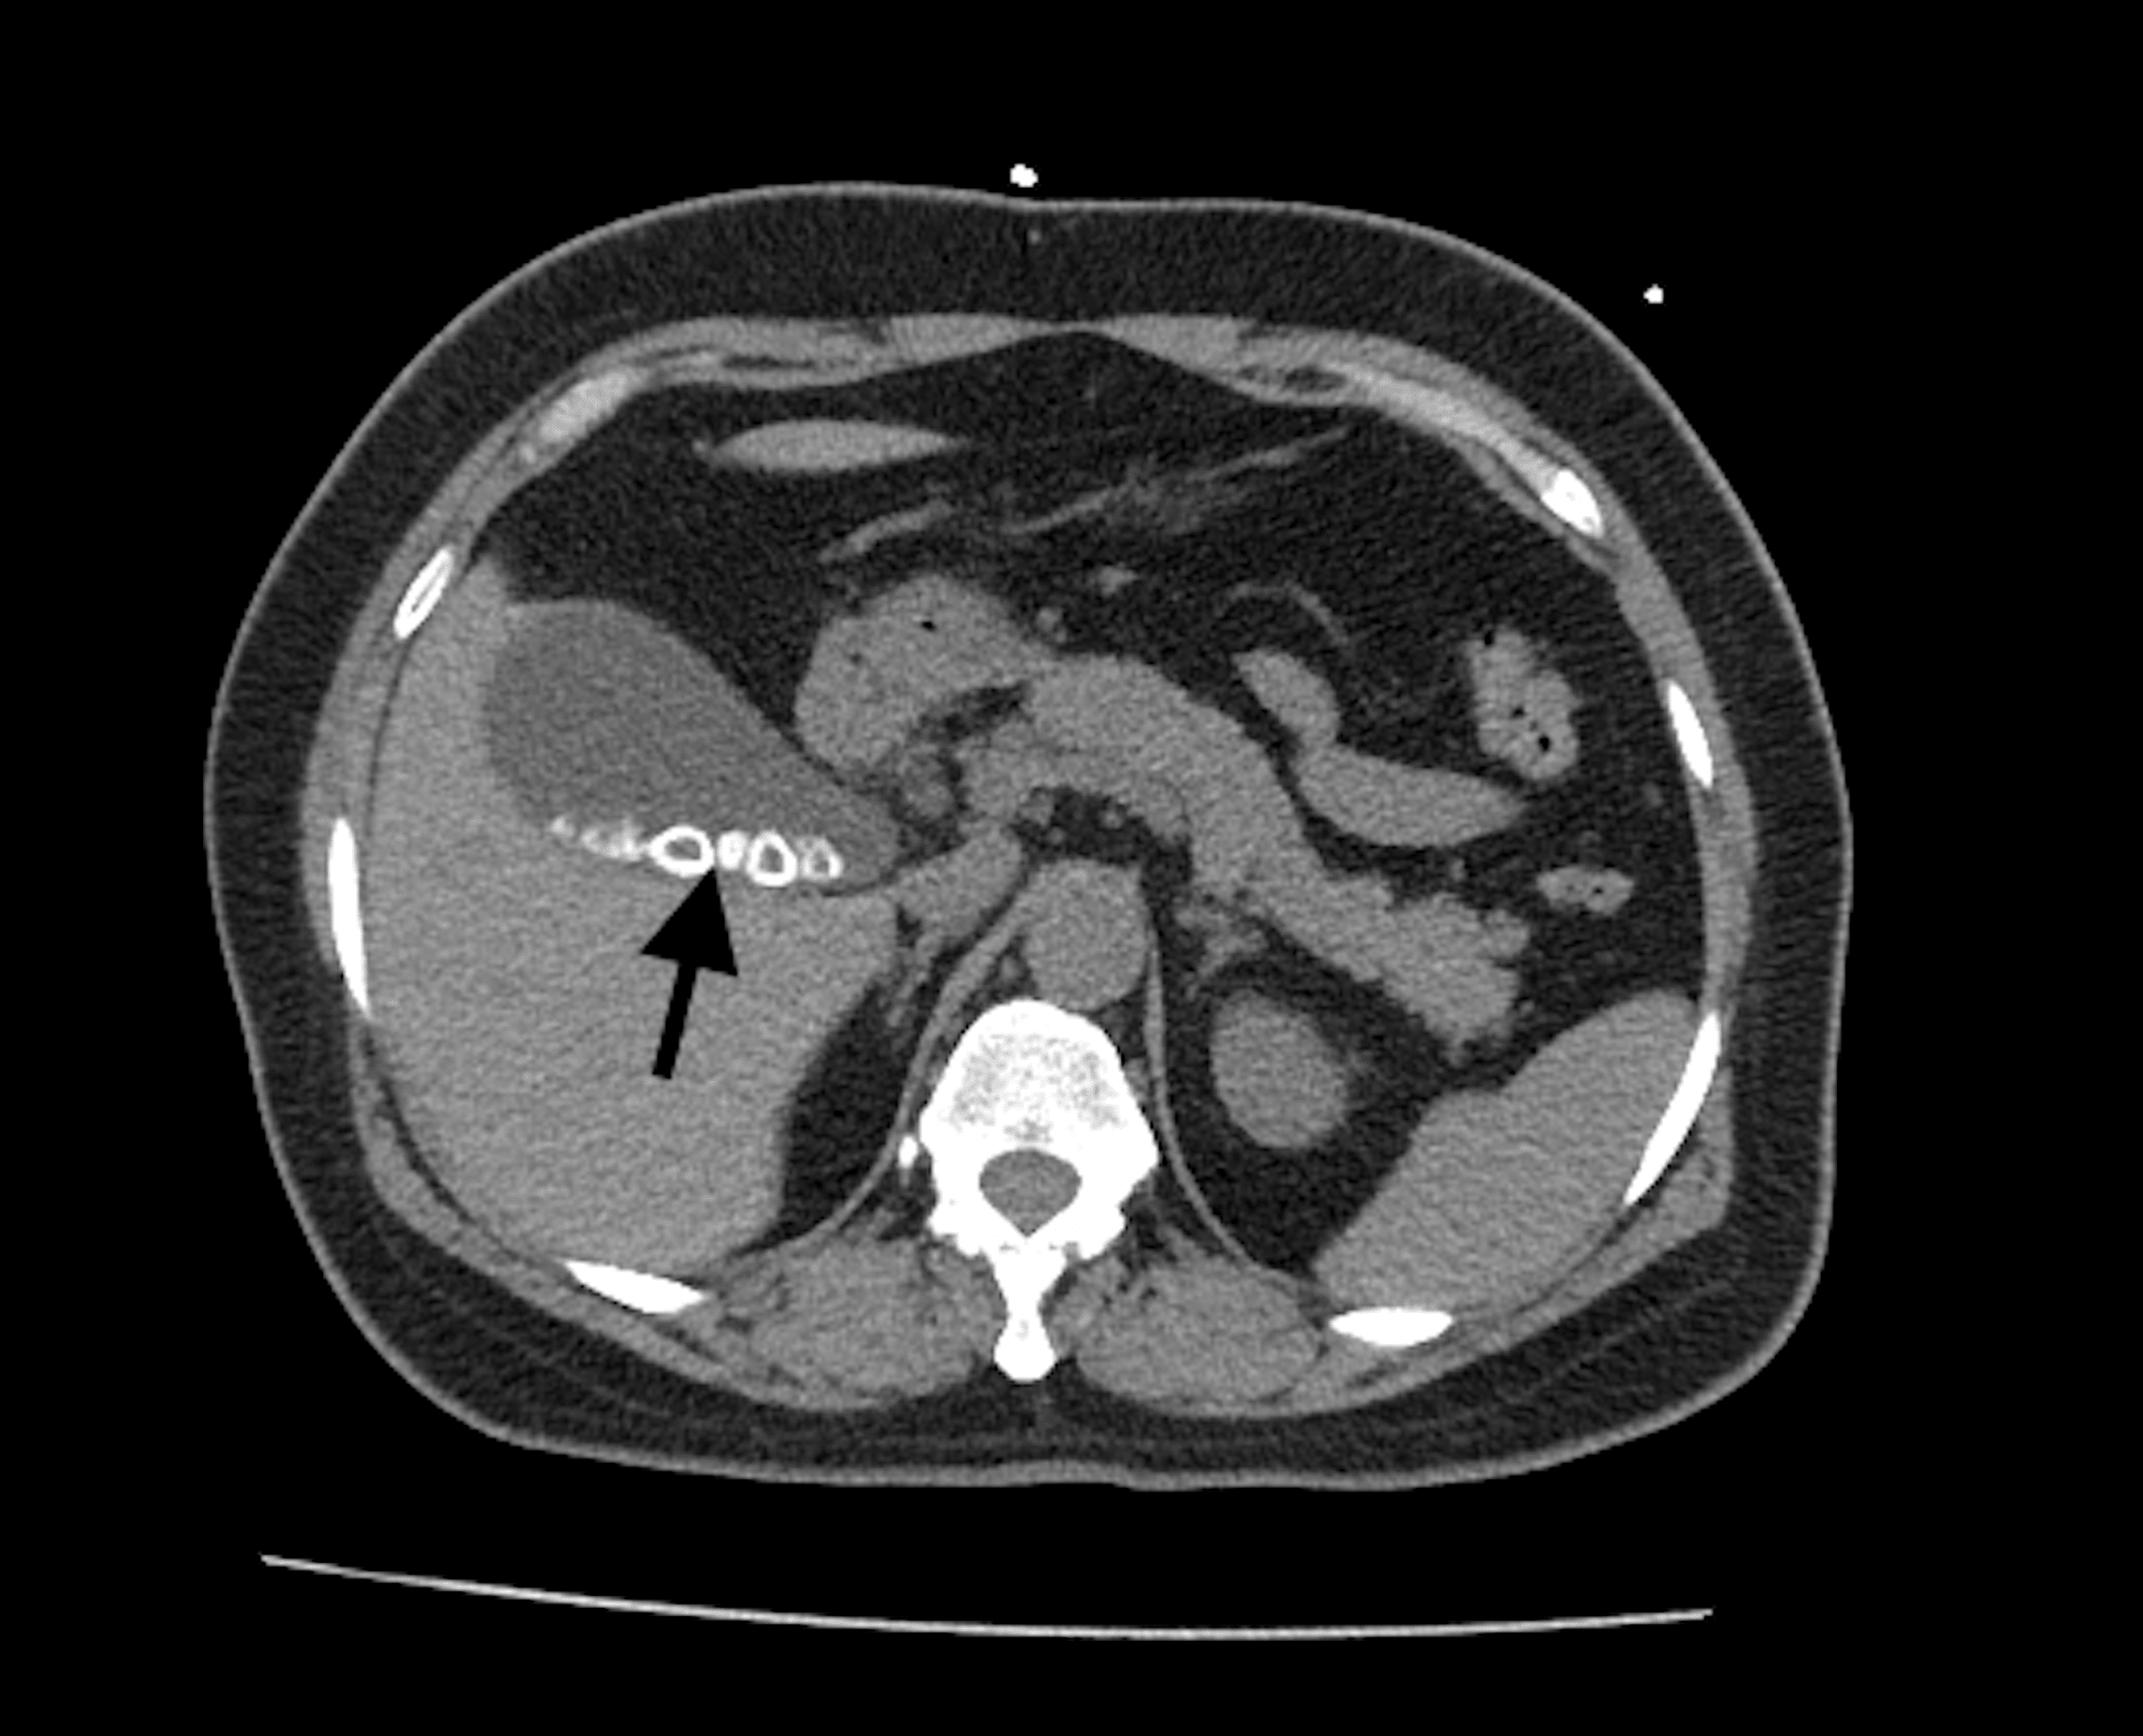

Axial CT noncontrast demonstrates gallstone (black arrow) fistulated Non Radiopaque Gallstones Gallstones (cholelithiasis) describe stone formation at any point along the biliary tree. Are gallstones the likely cause of my abdominal. Gallstones and gallbladder cancer are the two most prevalent benign and. For gallstones, some basic questions to ask your doctor include: Gallbladder disease is common in clinical practice. Specific names can be given to gallstones depending on their location: Most. Non Radiopaque Gallstones.